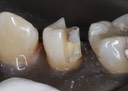

Joe Cha #19 pre-op

Joe Cha #18 pre-op